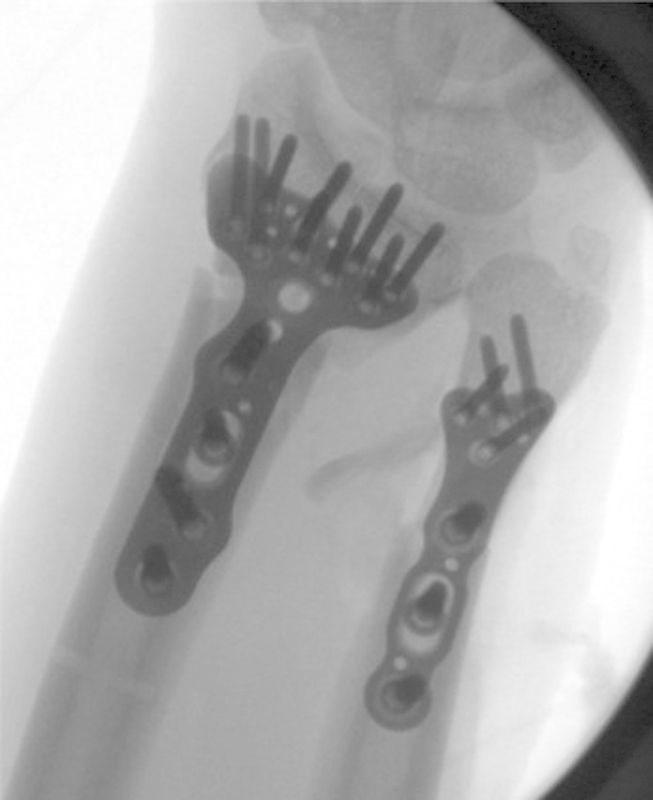

Fig. 20.

Posterior/anterior radiographs shows anatomic restoration to the joint surface.

Fig. 21.

Lateral radiograph demonstrating a plate sandwich with anatomic restoration to the very comminuted intra-articular fracture to the distal radius.